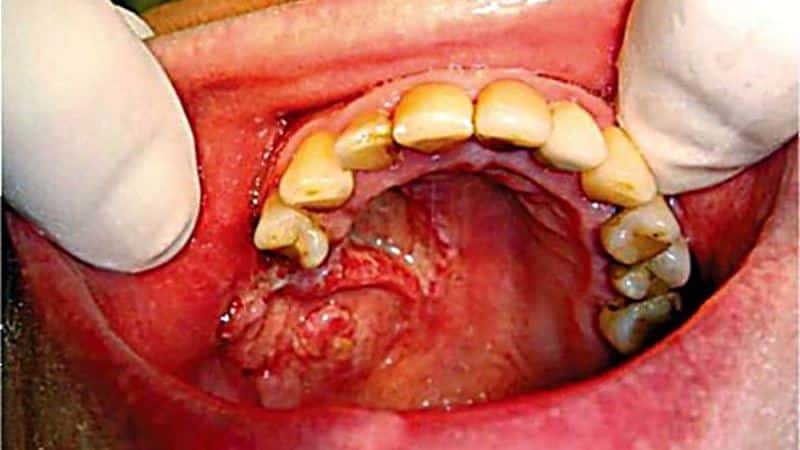

Симптомы альвеолита

Итак, после того как вырвали зуб, лунка, особенно если она сухая (без кровяного сгустка), может загноиться уже на 2 день после процедуры. При этом вначале нет острой боли, а появляется лишь слабая ноющая боль, усиливающаяся во время еды.

В лунке при этом нередко определяются остатки пищи и слюны. Края десны на месте удаленного зуба красного цвета, при прикосновении к ним возникает боль. Общее состояние человека при этом удовлетворительное, температуры нет.

При дальнейшем распространении гнойной инфекции развиваются уже более характерные симптомы альвеолита:

- сильная постоянная боль на месте удаленного зуба;

- распространение (иррадиация) боли на соседние области – от челюстно-лицевой зоны до зоны головы;

- повышение температуры тела до относительно высоких значений (до 38) и появление связанных с этим озноба, ощущения ломоты в теле и ухудшения общего самочувствия;

- появление гнилостного неприятного запаха изо рта в результате нагноения лунки;

- отсутствие в ране кровяного сгустка (сухая лунка);

- наличие грязно-серого налета на поверхности заживающей десны (иногда наблюдается черная лунка);

- увеличение подчелюстных лимфатических узлов;

- один их важных и характерных признаков нагноения лунки на месте удаленного зуба – появление гнойного экссудата из раны, особенно при нажатии на десну.

Обратите внимание! Внешне альвеолит выявляется также легко. Если сгусток начал разрушаться и загнивать, на поверхности раны будет грязновато-серая пленка с зеленым оттенком. Если же тромб выпал или не сформировался, станет заметна костная ткань.